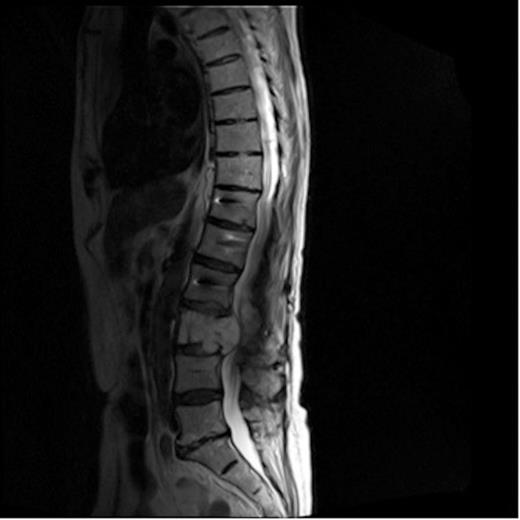

A 72-year old man presented with an 8-month history of lower back pain and increasing left leg pain and weakness. An abnormal appearance of the L3 vertebral body on plain radiographs prompted CT investigation which suggested pathological fracture of L3 with posterior convexing of the vertebral body and epidural mass. Also noted was a mass within the right kidney which was felt to be in keeping with the appearances of renal cell carcinoma. MRI confirmed a solitary vertebral lesion causing posterior convexity of the vertebral body with extension into the pedicle, causing significant compression of the thecal sac and clumping of nerve roots. The patient was commenced on Dexamethasone. Based on the radiological presumption that this was a secondary deposit from a renal cell carcinoma within the right kidney, plans were made for posterior spinal decompression and stabilisation, and tissue biopsy was felt to be unnecessary. Pre-operative embolization of the tumour was attempted, however, no tumour enhancement was demonstrated during the aortogram, and embolization was therefore not performed. Decompression and posterior stabilisation from T12 to L5 was performed and biopsies of L3 sent for analysis. The biopsy revealed trabecular bone and marrow fat replaced by malignant tumour, in-keeping with chordoma, not the presumed diagnosis of renal cell carcinoma.

MRI of lumbar spine showing mass causing compression of the cauda

The patient developed an ileus post-operatively but soon settled and his lower back pain gradually improved. Following discharge, a plan was made for further investigation of the renal lesion. Unfortunately his lower back pain returned 6 months later, and subsequent imaging showed enlargement of the lumbar spine mass causing further compression of the cauda. (Figure 1). This subsequently required further surgery in the form of tumour debulking with anterior stabilisation of L3. Investigation of his renal mass is on-going.